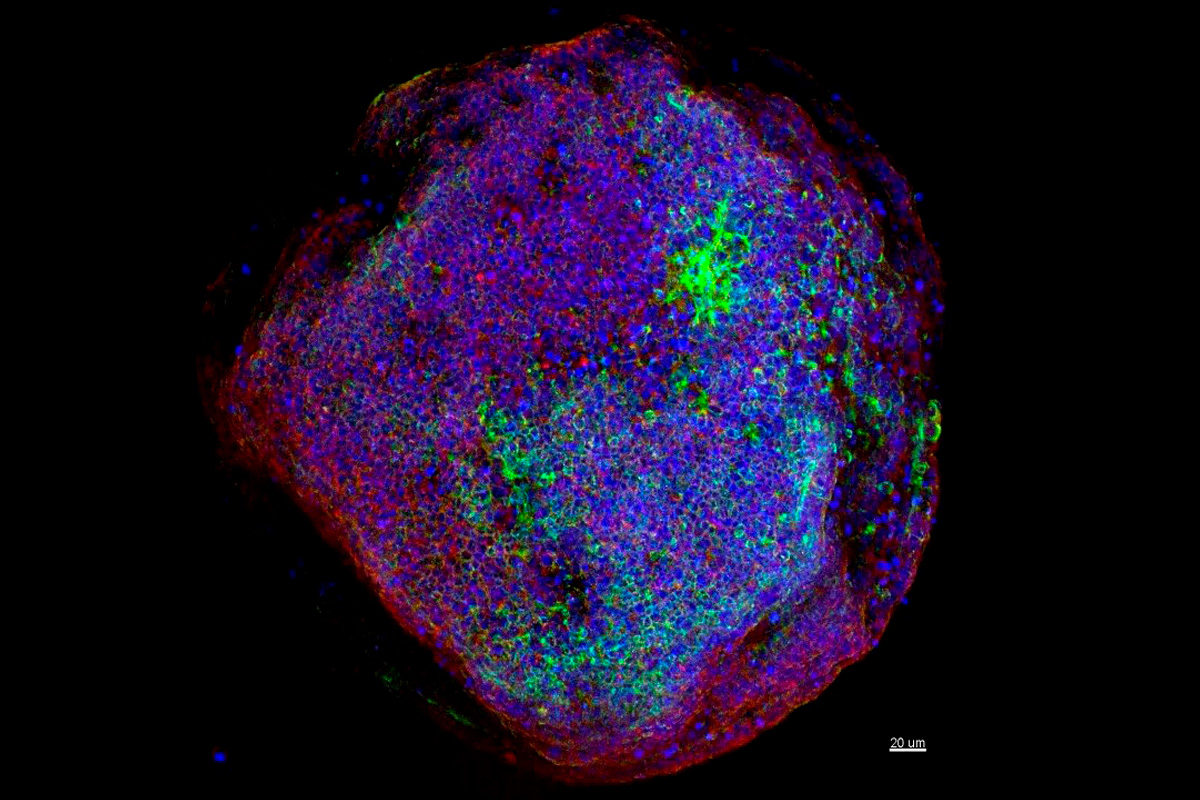

Immunofluorescence of tumoroids using antibodies. Mouse colon tumoroids stained with CK14 (green), CK8/18 (red) and DAPI (blue)